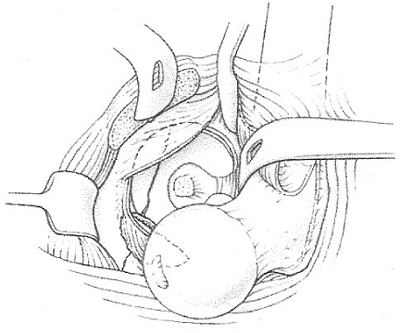

![]() |

Figure 44.7. Dislocation of hip with exposure of femoral head and Pipkin fragment.

femoral head. A surgical dislocation was performed. He was found to

have a sagittal split involving one third of the weight-bearing surface

of the femoral head (Fig. 44.12). The